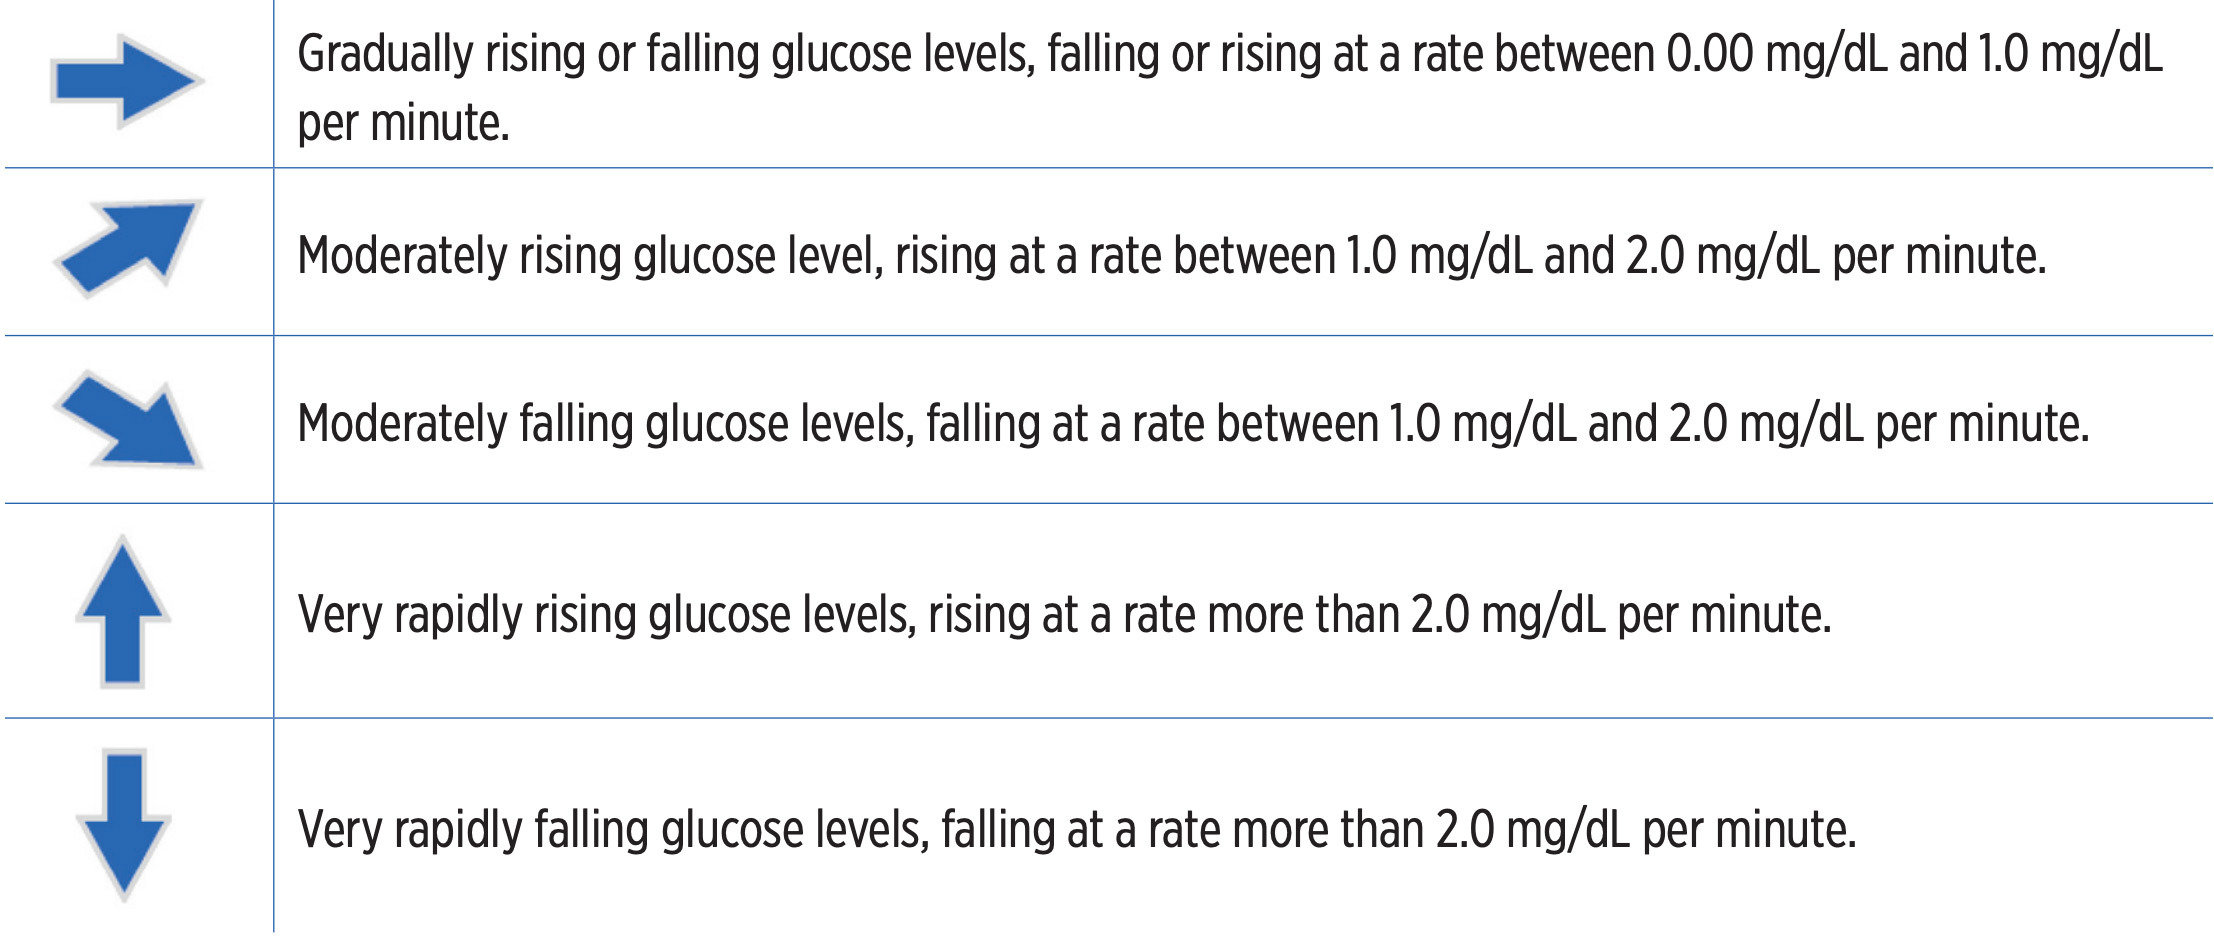

Los distintos ángulos de la flecha hacen referencia a una velocidad de cambio distinta, como se muestra en el gráfico de la derecha:

- estable;

- aumentando moderadamente;

- descendiendo moderadamente;

- aumentando con mucha rapidez;

- y descendiendo con mucha rapidez.

Niveles de glucosa que aumentan o descienden gradualmente, a una velocidad de entre 0,00 mg/dL

y 1,0 mg/dL por minuto.

Niveles de glucosa que aumentan moderadamente, a una velocidad de entre 1,0 mg/dL y 2,0 mg/dL por minuto.

Niveles de glucosa que descienden moderadamente, a una velocidad de entre 1,0 mg/dL y 2,0 mg/dL por minuto.

Niveles de glucosa que aumentan con mucha rapidez, a una velocidad superior a 2,0 mg/dL por minuto.

Niveles de glucosa que descienden con mucha rapidez, a una velocidad superior a 2,0 mg/dL por minuto.

FLECHAS DE TENDENCIA